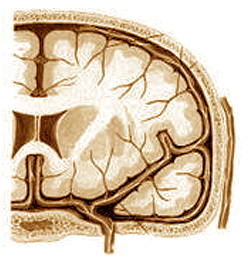

Mecanismul migrenei

Se cunosc 3 etape ale tulburării vasomotorii:

1. Totul începe printr-un spasm arterial (foto 1) care va reduce fluxul sanguin într-o parte a creierului. În acest moment bolnavul vede neclar, şters, percepe în câmpul vizual pete întunecate sau strălucitoare (scotoame), dar încă nu apare durerea. Se înregistrează eliberarea de catecolamină (hormonii stresului) din suprarenale.